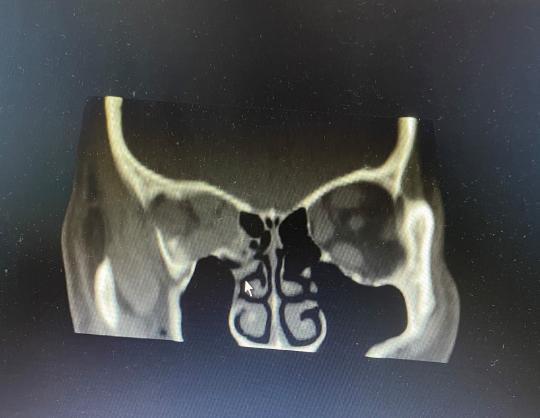

眼科主任中医师孙利为杨大伯做了眼眶CT检查,确诊其为Graves眼症(甲状腺功能亢进性突眼症)。这种疾病会导致眼睛不能完全闭合,结膜、角膜外露引起充血、水肿、角膜溃疡等,严重甚至会因为眶压高而压迫视神经导致失明。视力检查测得杨大伯左眼视力0.4,右眼0.08,孙利主任表示,如果不能及时减轻眶压,导致视力持续下降,很可能导致失明,考虑到杨大伯的个人情况,再综合分析病情,孙利主任建议其尽快手术。经过与杨大伯的反复沟通和商议,最终决定为其行“右眼眼眶减压手术”。

术后眼眶CT造影

由于手术部位深及眶尖部位,紧邻视神经管、眶上裂等重要颅底结构,并需要磨除一部分颅底骨质,手术有一定风险。为保证杨大伯双眼眼压的基本一致,手术由眼科孙利主任和神经外科张勇主任同台协作,共同为患者保驾护航,历经2个小时的奋战,手术终于顺利完成。出院时,杨大伯的右眼视力得到明显改善,由原来的0.08恢复到0.1,术后2周来医院复查,视力逐步恢复到0.25,术后第3周恢复到0.4,现在杨大伯的两眼视力已基本相同。在手术缝合时,孙利主任运用了美容缝合技术,如今杨大伯的眼睑处几乎看不出手术的痕迹,杨大伯对此也非常满意。